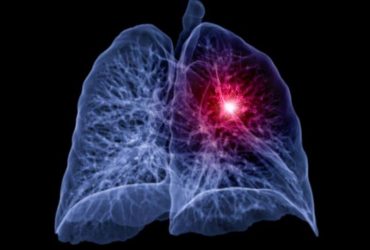

Complication rates substantially higher after abnormal findings with low-dose CT lung cancer screening versus those seen in National Lung Screening Trial

Sybil achieved areas under receiver operating characteristic curve of 0.92, 0.86, and 0.94 on three external validation sets

More than 50 cancer groups have issued an urgent call for more lung cancer screening among high-risk people

Promoting low-dose CT screening among mostly nonsmoking women increased detection of early-stage, but not late-stage, lung cancers